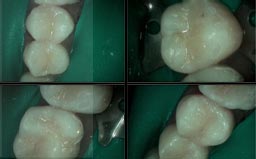

At Gramercy Smiles we are dedicated to creating lasting smiles through comprehensive care using the latest technology. We proudly offer personalized, patient-driven care focused on the health, beauty, and functionality of your teeth. Please browse our smile gallery below and contact us to schedule a smile consultation today.